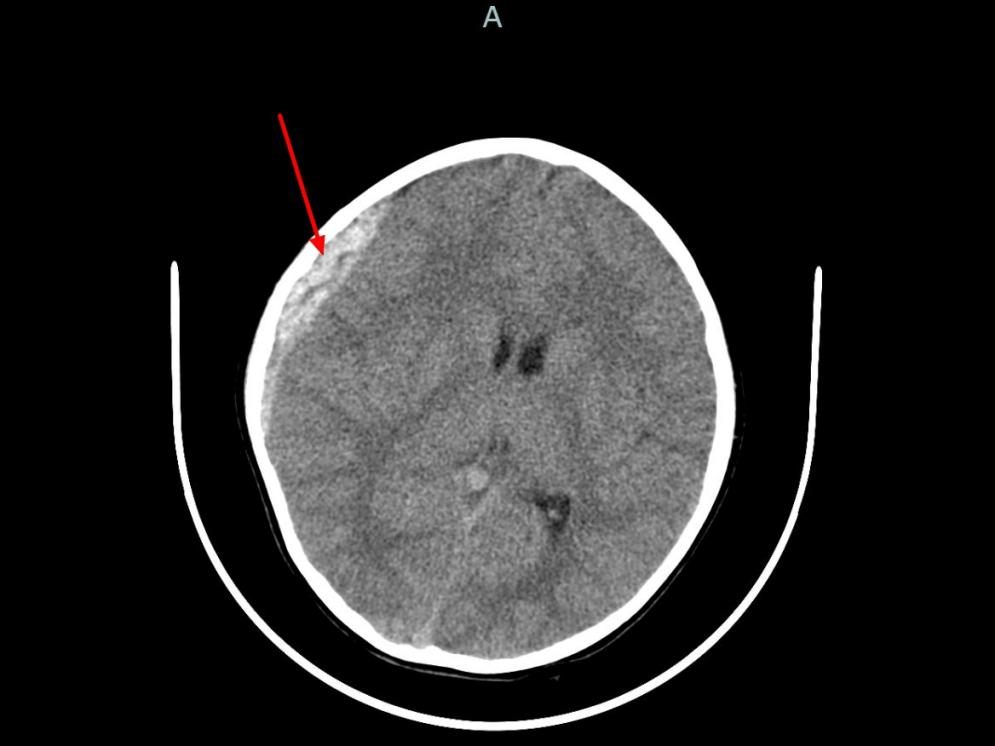

颅前窝骨折的临床表现

3嗅觉障碍颅前窝骨折可能损伤嗅神经,导致嗅觉减退或完全丧失嗅神经位于筛板区域,骨折时易受牵拉或压迫,进而影响嗅觉功能这一症状对诊断具有辅助意义,但需结合其他临床表现综合判断4眶上及眶内骨折骨折可累及眶上缘或眶内结构,...